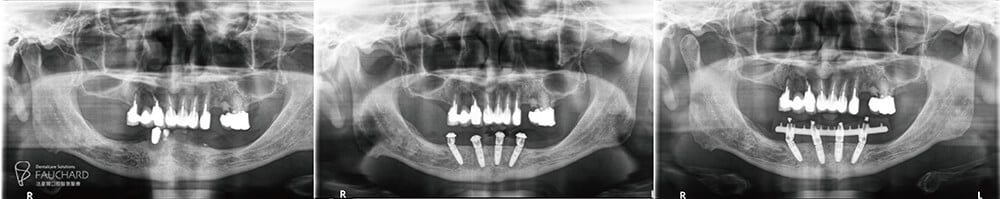

下顎 All-on-4 全口重建術前術後對比